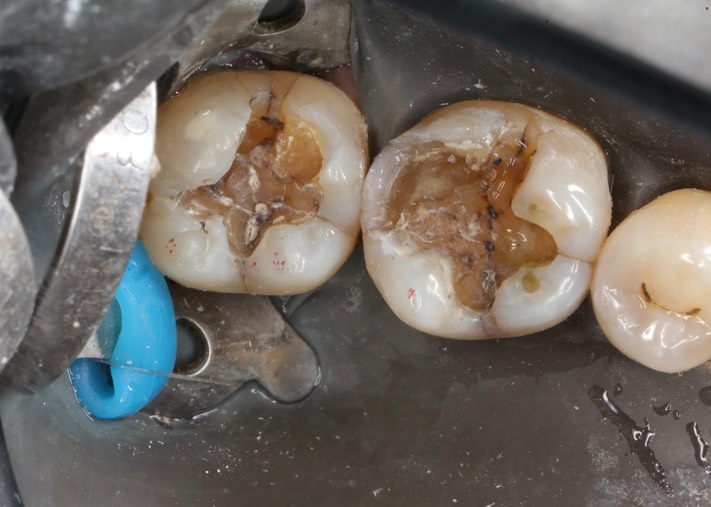

Kyle Chock #30-31 amalgam removal

Kyle Chock #30-31 amalgam removal 3